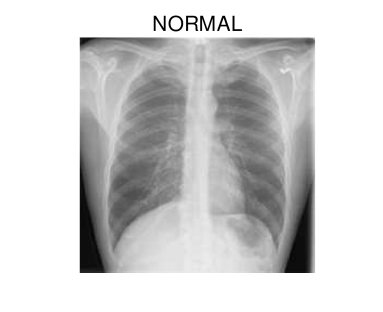

In hospitals, chest X-rays can mitigate these drawbacks by enabling a fast and reliable diagnosis. Figure 1 shows chest X-ray scans of healthy (top) and COVID-19 (bottom) patients in direct comparison. Even though patchy consolidations are recognizable in the COVID-19 scans, such X-rays remain challenging to interpret. Specialists, however, are able to identify the severity of a case early on and can take measures without waiting for lab results.